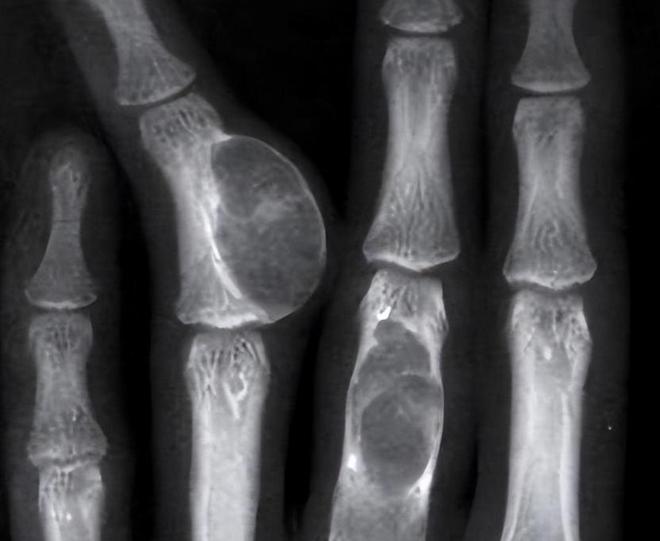

医生经过一番详细检查后,告诉李明馨和她的母亲:“你女儿的腿里发现了肿瘤,而且已经是恶性。”

癌症?他们根本无法相信,一个平时活泼开朗、成绩优异的少女,怎么可能患上这样严重的疾病?